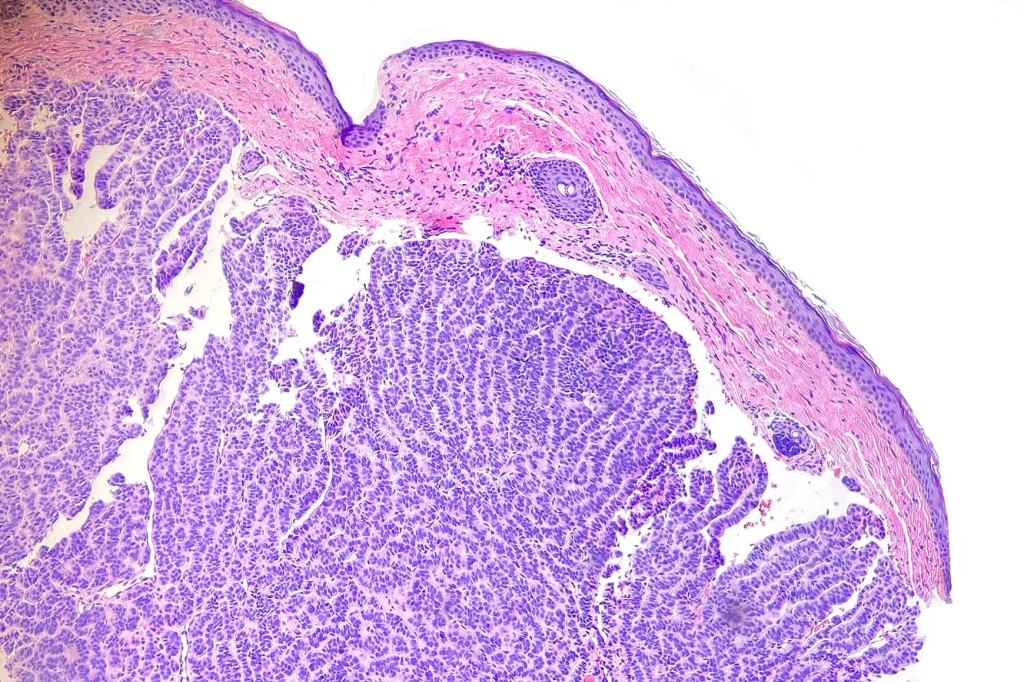

Histological features

•Variable continuity with epidermis

•Multinodular with surrounding collagenous stroma

•Random distribution of basaloid cells & sebocytes (<50% sebocytes)

•Absent peripheral palisading & retraction artifact